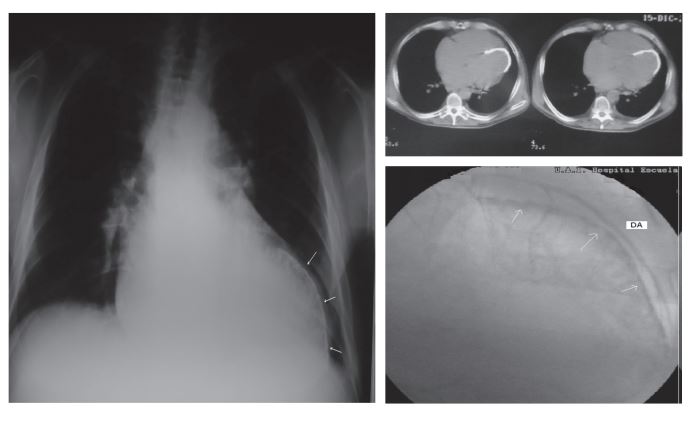

Calcificación del ventrículo izquierdo